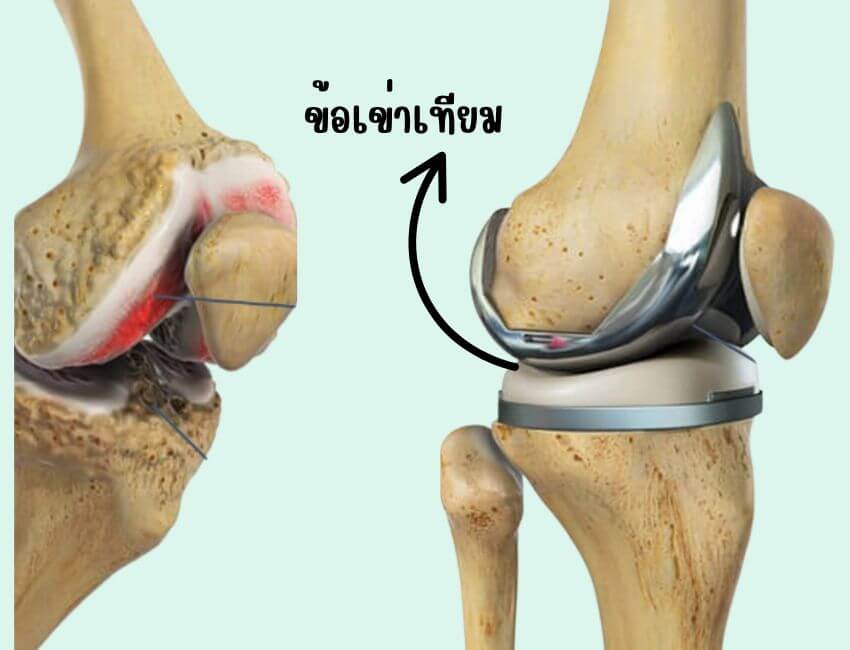

ระยะสุดท้าย ถ้าไม่ได้รับการแก้ไข จะเกิดการสลายของเซลล์ผิวกระดูกอ่อน สูญเสียโปรตีนและของเหลวในข้อเข่า (synovial fluid) ทำให้เกิดการโก่งผิดรูปของข้อเข่า ข้อเข่าจะไม่สามารถเคลื่อนไหว งอเหยียดเข่าได้เหมือนปกติ

- แก้ไข คงสภาพ และฟื้นฟูสภาพการทำงานของข้อให้ใกล้เคียงปกติมากที่สุด โดยการทำกายภาพบำบัด และอาจต้องมีการผ่าตัดเปลี่ยนข้อเข่า โดยใช้ข้อเข่าเทียมแทนในผู้ป่วยบางรายด้วยถ้าจำเป็น